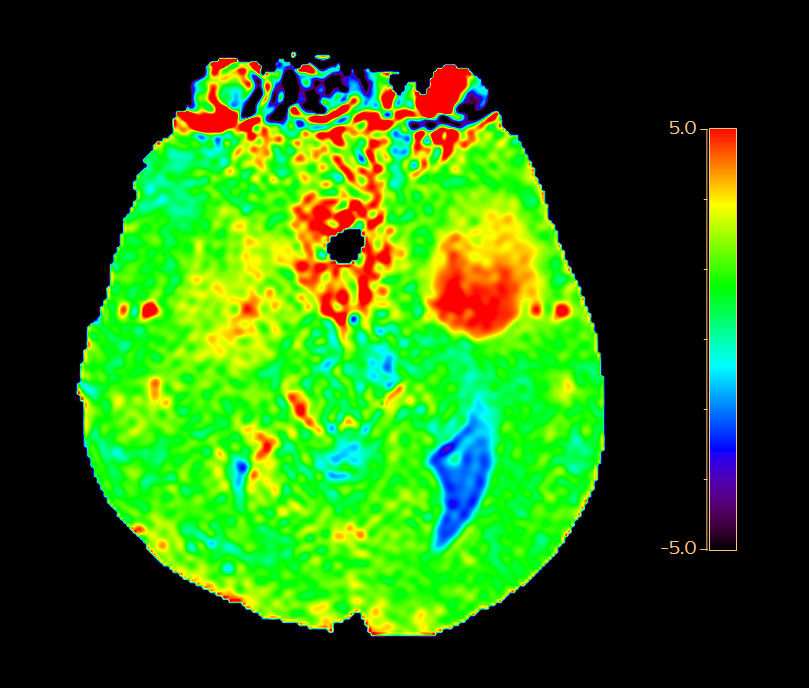

Axial 3D APT

-